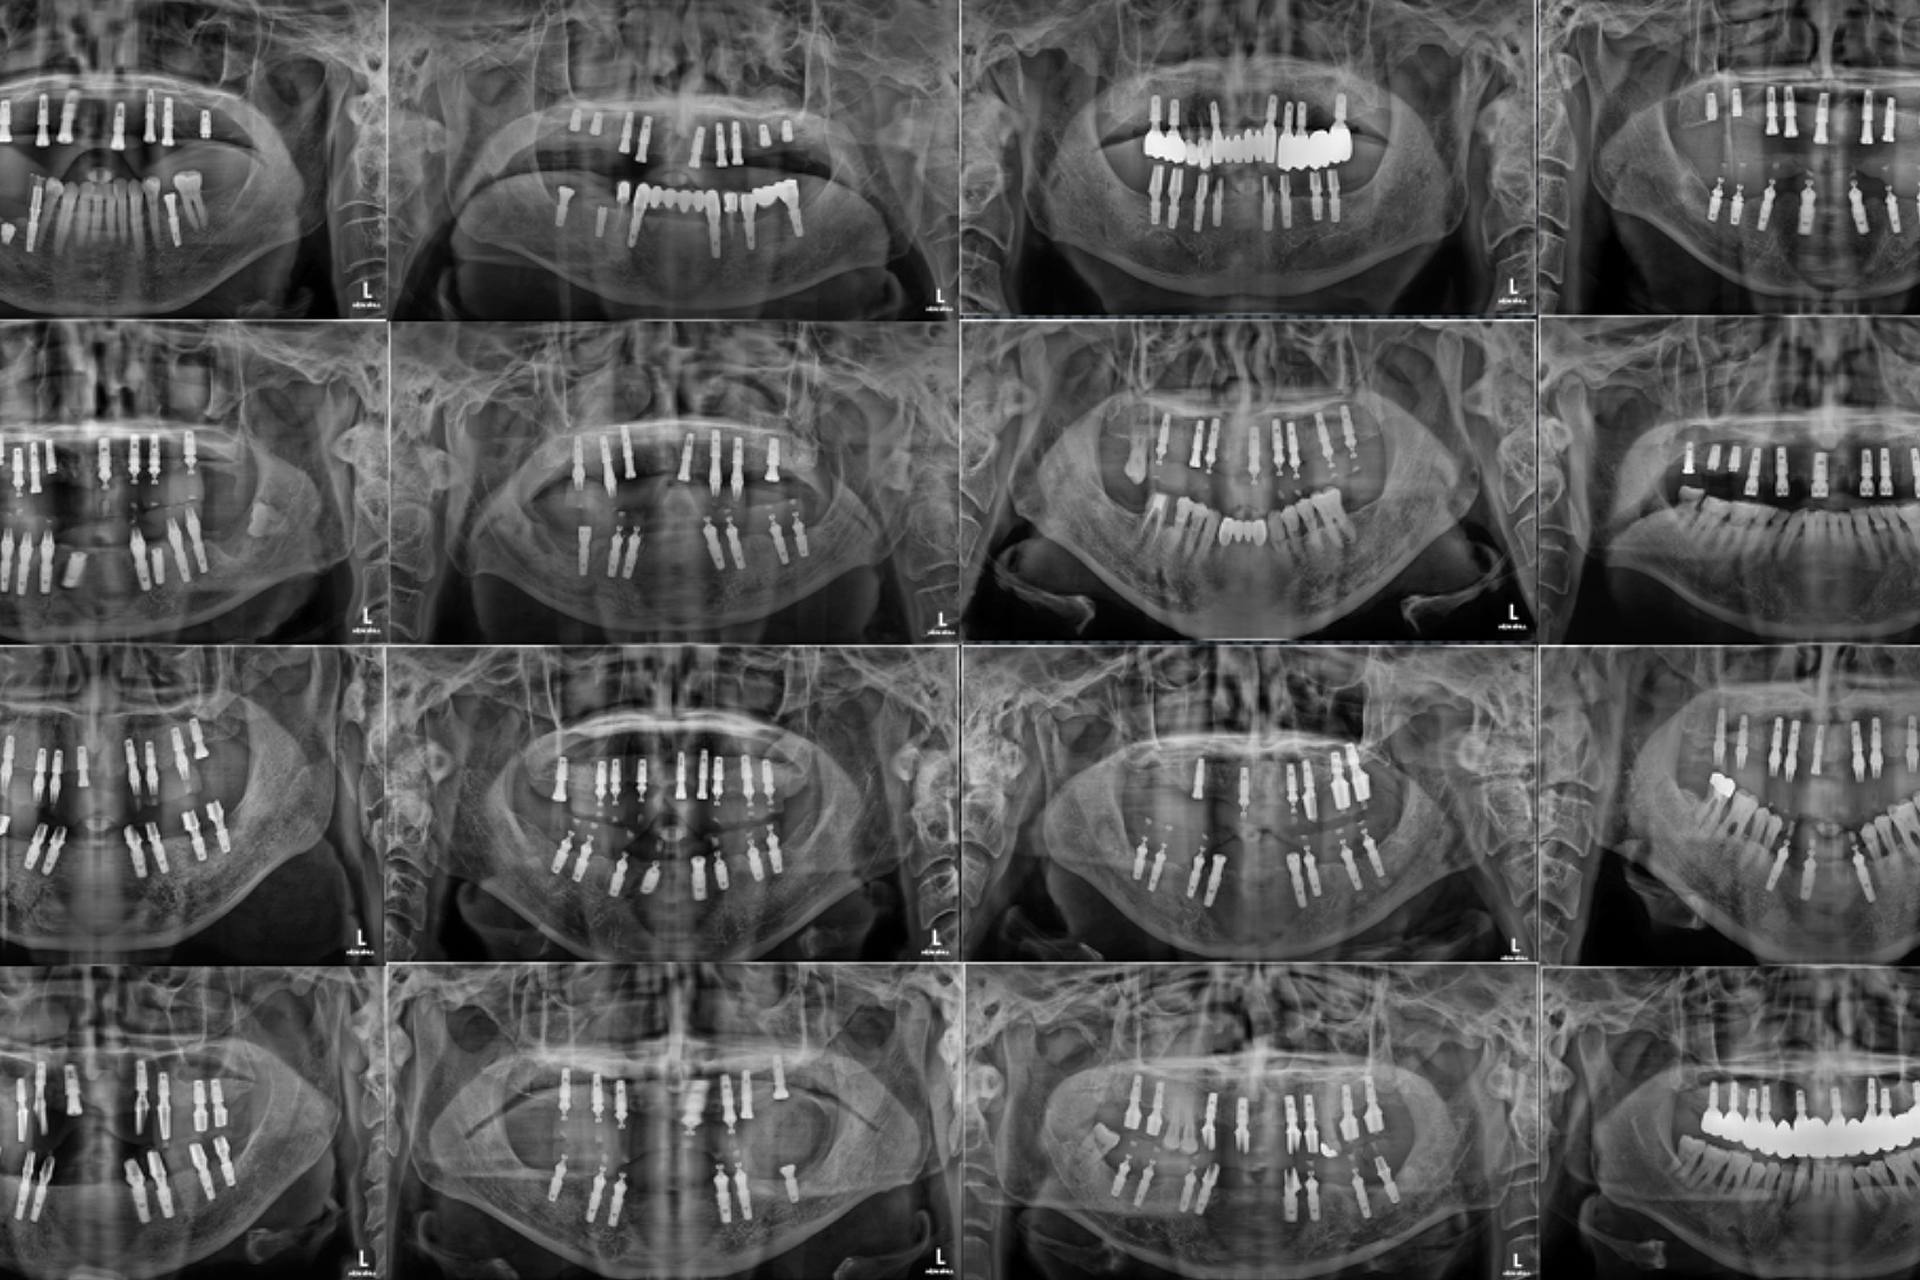

또 직접 제작한 네비게이션 가이드를 이용해

수술하기 때문에 절개량이 작아 출혈과 통증이 적고,

정확하고 안전하게 식립 가능합니다.